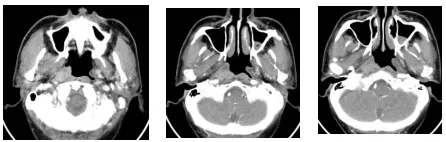

2017年7月患者于另一家医院进行系统住院治疗。住院后鼻咽部CT显示右侧鼻咽部咽隐窝消失,侧壁黏膜增厚,动脉期轻度强化,延迟区显著强化,病变周围脂肪间隙完整,骨组织未见破坏。临床诊断:鼻咽低分化鳞癌;右肺上叶周围型肺癌可能性大;双肺多发转移可能性大。临床治疗方案:多西他赛联合顺铂的全身化疗。经过4个周期化疗后影像评估发现鼻咽部肿瘤略缩小,无显著变化;而肺内病变化疗前后几乎没有变化。考虑到化疗效果不明显,临床对鼻咽部肿瘤进行放射治疗。计划剂量70Gy,分35次照射。

图三:2017.7化疗前(鼻咽部肿物)

图四:2017.11化疗评估(鼻咽部肿物)略有缩小